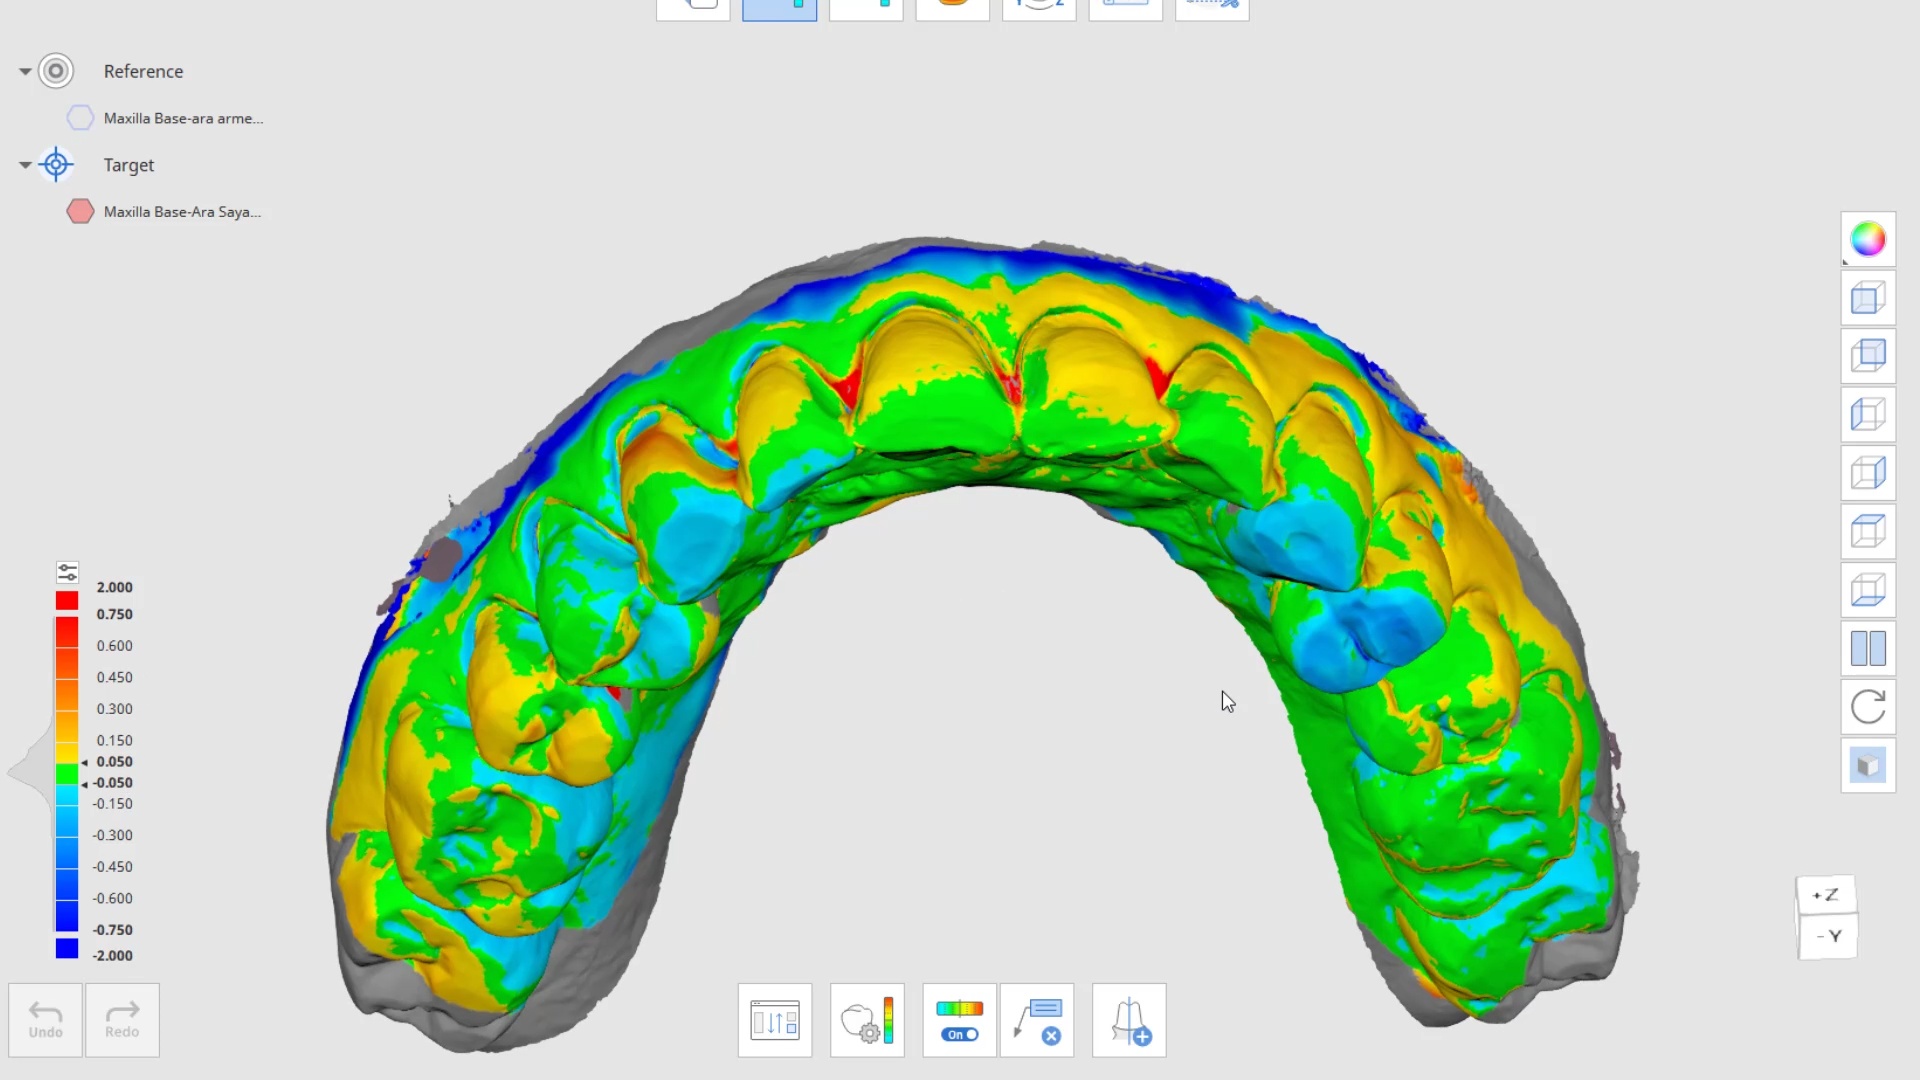

March 17, 2022the patient was sedated and intubated for the case so we could not keep track of the bite. Instead, we imaged all 30 prepared teeth and used medit compare […]

the patient was sedated and intubated for the case so we could not keep track of the bite. Instead, we imaged all 30 prepared teeth and used medit compare […]